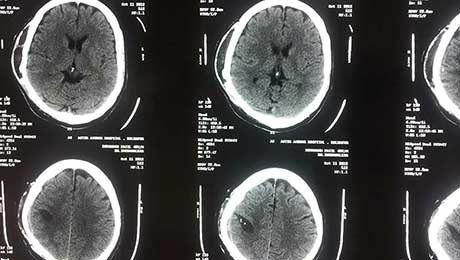

Post Op 1 CT Scan